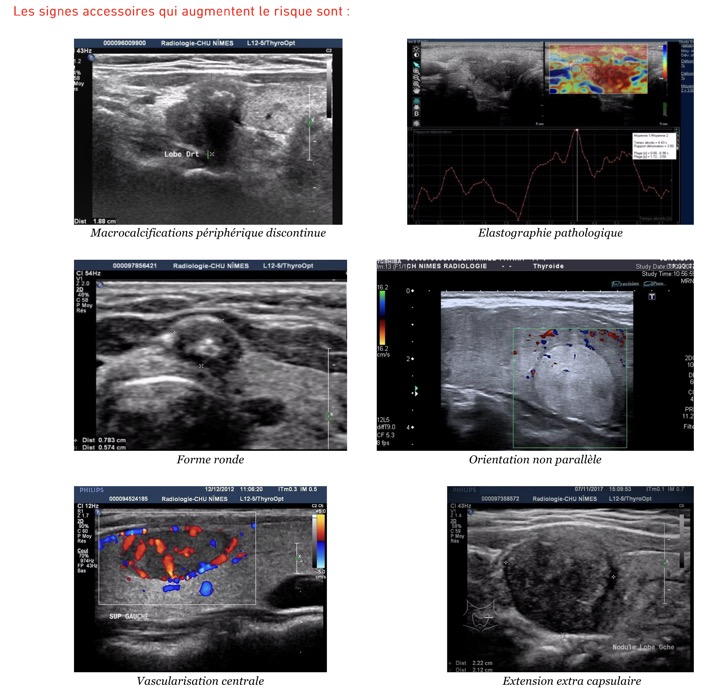

Nodules thyroïdiens

Se méfier des formations hypoéchogènes